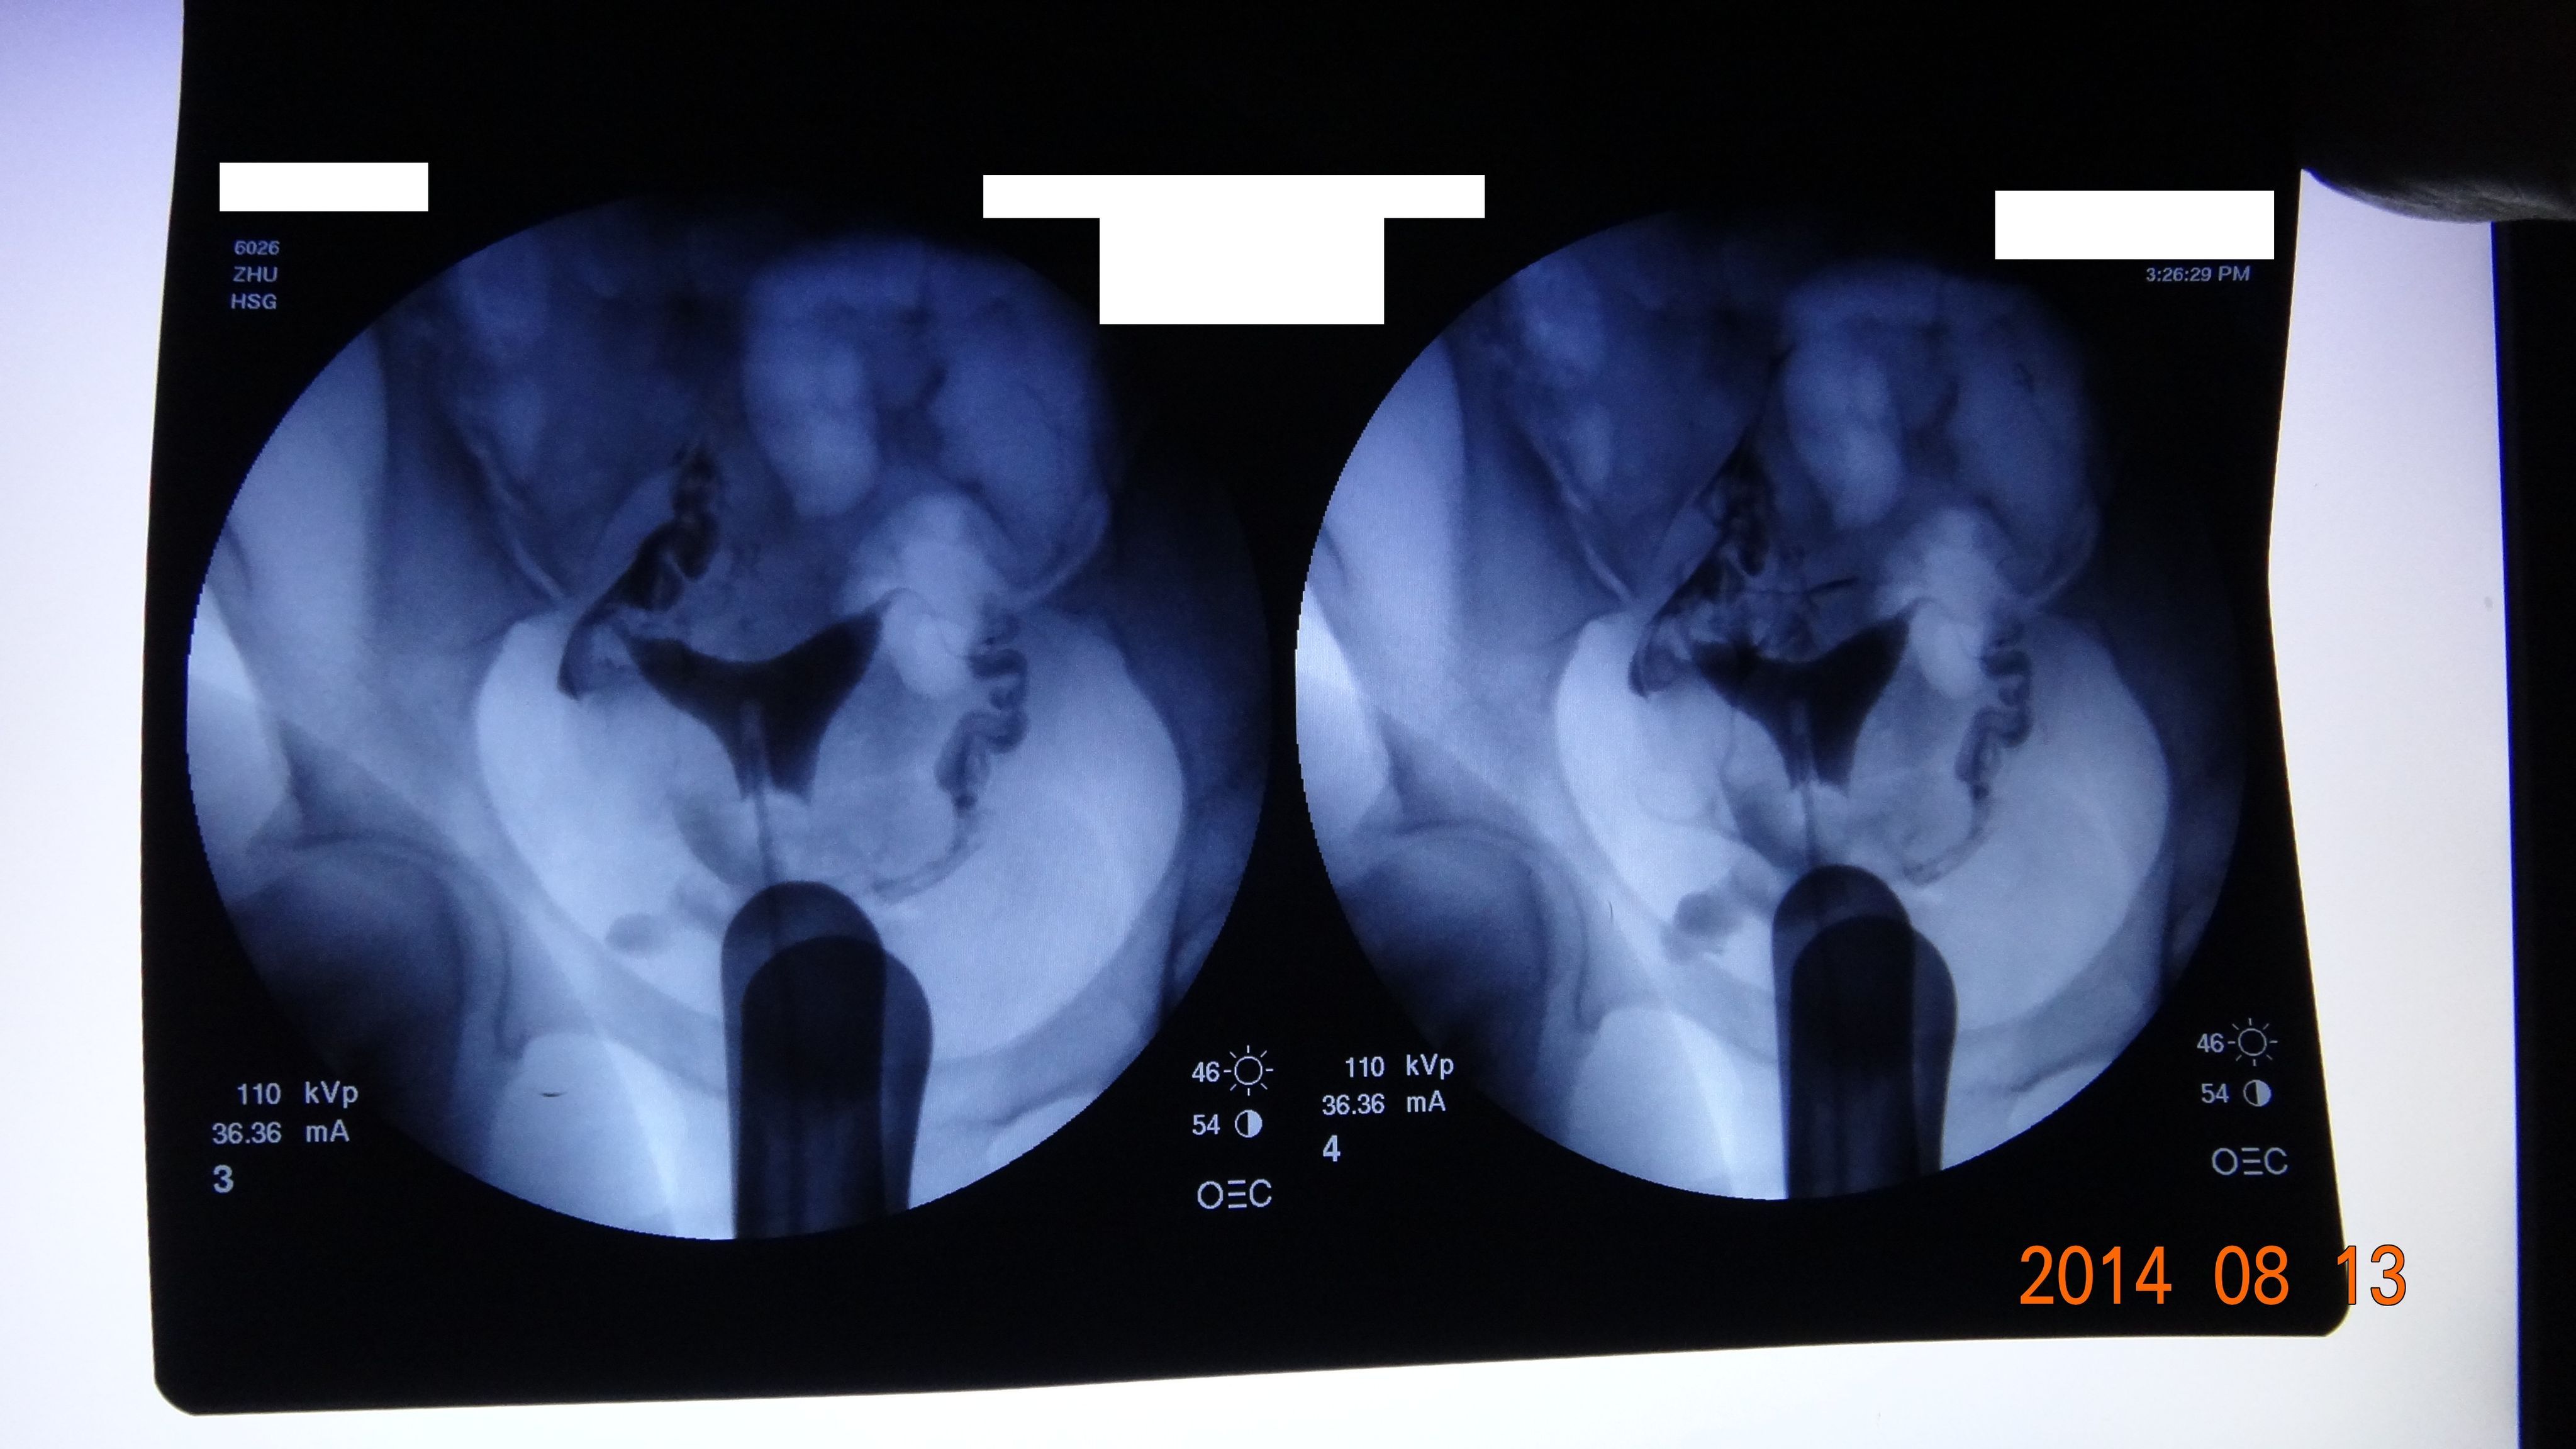

有没有会看输卵管造影片子的大神??100高分悬赏,谢谢,有急用!!万分感谢!! 请详细描述下:左右输卵管通畅与否,是否有黏连阻塞?此形态的子宫输卵管会影响生育否?还有没有其他能看到的问题 请一并叙述之.请尽量客观且通俗的讲解,谢谢大家,此片子非常重要,万分感谢所有参与回答的大家!!! 点击展开 母婴用户520887914 2014-08-13 17:42 推荐回答 如果您着急,瓣乐为什么不去医院崇惠贸呢!网上很多人都是不峡葛负责任的乱说,不要轻信~!希望你健健康康 匿名用户 2014-08-13 20:45 宝宝知道提示您:回答为网友贡献,仅供参考。 相关问题 输卵管造影后的片子,请专家看看…50分 万分感谢 一个输卵管造影的片子,大家看看有问题吗?请教教? 请帮忙看子宫输卵管造影报告,万分感谢!

请详细描述下:左右输卵管通畅与否,是否有黏连阻塞?此形态的子宫输卵管会影响生育否?还有没有其他能看到的问题 请一并叙述之.请尽量客观且通俗的讲解,谢谢大家,此片子非常重要,万分感谢所有参与回答的大家!!!